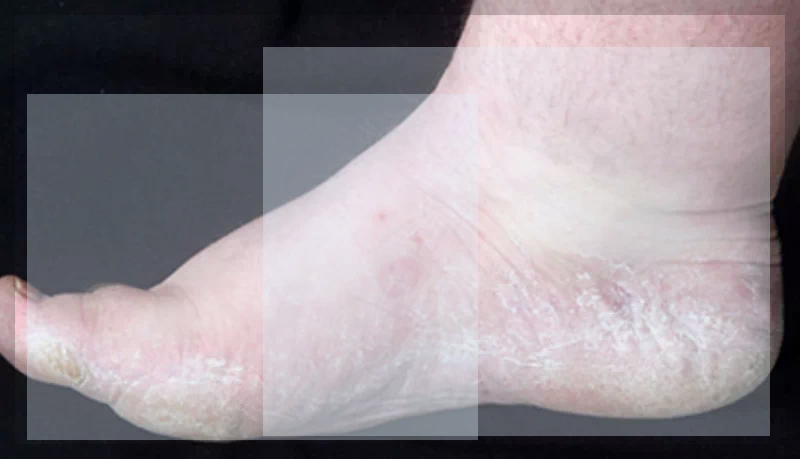

무좀의 주요 증상으로는 발바닥과 발가락 사이의 가려움증, 발적, 피부 갈라짐, 그리고 피부가 두꺼워지는 현상이 있습니다. 이러한 증상은 시간이 지남에 따라 악화될 수 있으며, 적절한 치료가 이루어지지 않으면 일상 생활에 큰 불편을 초래할 수 있습니다.

무좀은 발적과 피부 갈라짐을 유발할 수 있습니다. 발의 피부가 붉게 변하고, 심한 경우 피부가 갈라져 통증을 유발할 수 있습니다. 이러한 증상은 각질층이 두꺼워지면서 더욱 뚜렷해질 수 있습니다.

이 무좀의 또 다른 주요 증상은 피부가 두꺼워지는 것입니다. 각질층이 점점 두꺼워지며, 이는 발바닥과 발가락 사이에서 특히 두드러집니다. 두꺼워진 각질은 쉽게 갈라질 수 있으며, 이는 추가적인 통증과 불편을 초래합니다.